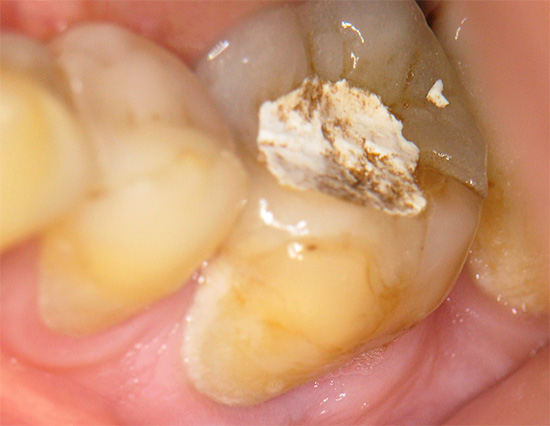

Nel tempo, il flusso può trasformarsi in una fistola (vedi foto):

Nelle forme croniche di parodontite, le formazioni più spiacevoli sulla gomma sono le fistole. Questi sono canali che si allontanano dalla radice infiammata del dente e da cui esce periodicamente un pus maleodorante, facilitando la sofferenza di una persona.